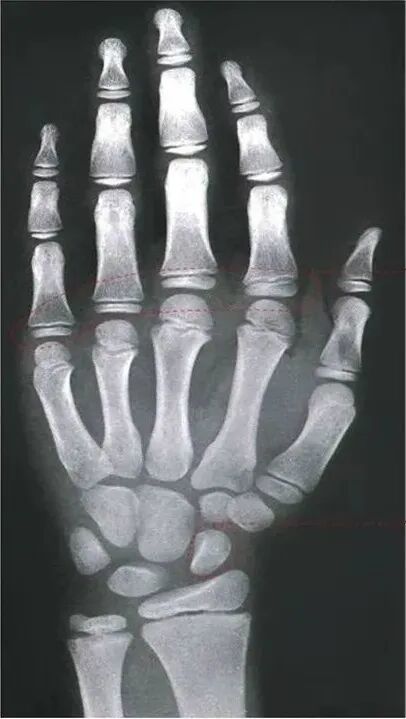

通过拍摄左手腕骨 X 光片,观察骨骺闭合状态是最准确的判断方式。

如果 X 光片显示骨骺线未闭合,说明仍有生长潜力;若已完全闭合,则身高基本定型。即使孩子实际年龄较小,但骨龄超前且接近闭合,生长空间也会受限。

图注:左图,骨骺未闭合;右图:骨骺已闭合